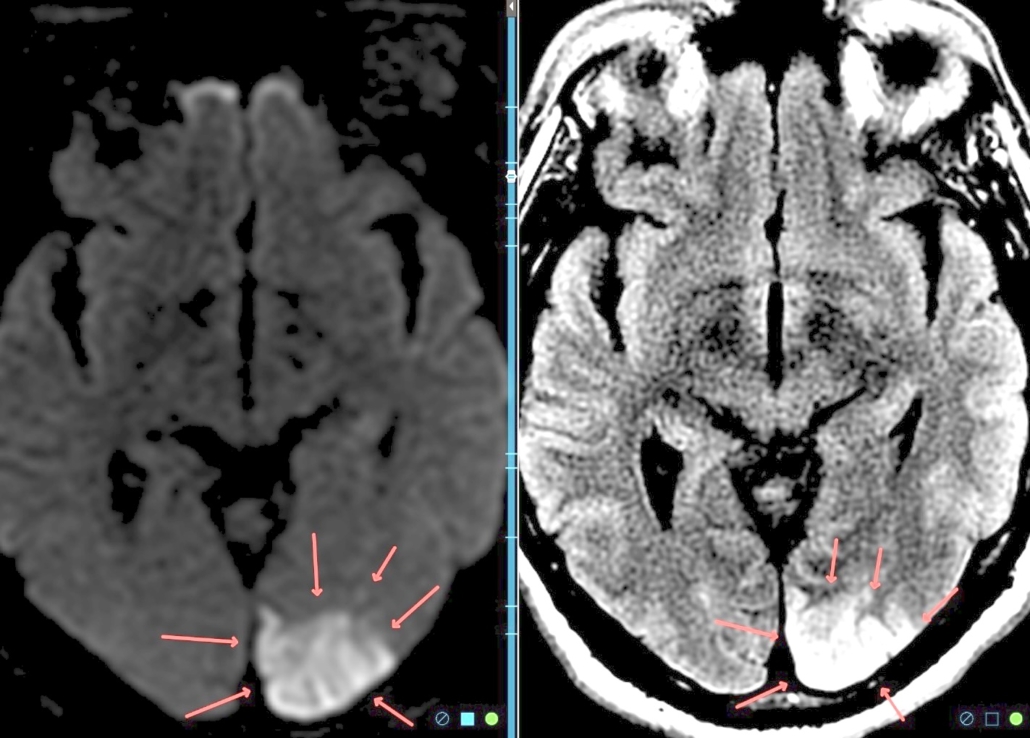

How can you have permanent brain damage from CO even after the carbon monoxide is removed from your blood? Because lack of oxygen can kill brain cells immediately (as shown here) and the delayed effects of the toxic assault on the blood brain barrier can kill brain cells for weeks and months.